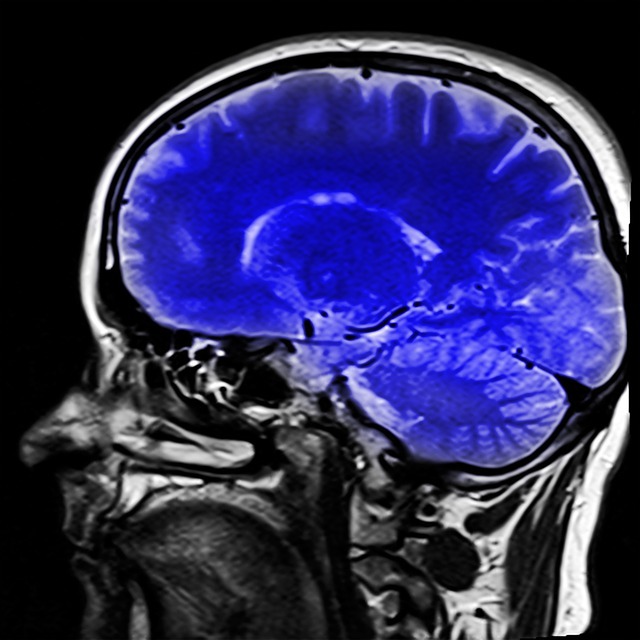

脳のレントゲン写真

kalhh

アフターケア制度は、労災で受けたけがの一部について、症状固定後も無料で診察や検査を受診できる制度です。

アフターケア制度の対象は、労災被害者の受けた、頭頸部外傷症候群や大腿骨頸部骨折、股関節脱臼・脱臼骨折、人工関節・人工骨頭置換など20項目です。労災事故以外でも、慢性肝炎や炭鉱災害による一酸化炭素中毒なども含まれます。